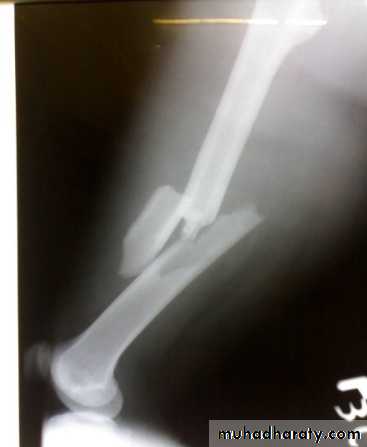

X-ray:

Usually there is some comminution.

X-ray of the pelvis and the knee to avoid missing injuries.